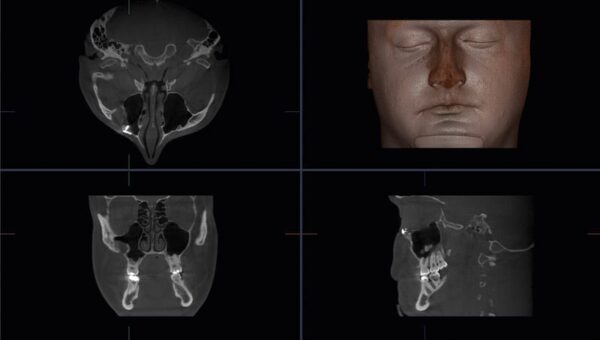

J. Morita Accuitomo 170 là hệ thống CBCT thế hệ thứ tư với trường chụp lớn nhất trong dòng Accuitomo — ø170 × 120 mm — cho phép tái tạo toàn bộ vùng đầu cổ trong một lần chụp. Đây là thiết bị CBCT được lựa chọn cho các ca lâm sàng phức tạp đòi hỏi độ phân giải cao nhất và liều tia tối thiểu.

Accuitomo 170 đạt voxel size tối thiểu 80 µm với 9 tùy chọn từ ø40 mm đến ø170 mm. Dải grayscale 14-bit — cao hơn hầu hết hệ thống CBCT thông thường — cho phép phân biệt tổ chức cứng và mềm, mô xương và mạch máu, đặc biệt có giá trị trong lên kế hoạch phẫu thuật phức tạp.

- Cấy ghép implant: đánh giá mật độ và thể tích xương hàm, vị trí ống thần kinh

- Phẫu thuật miệng hàm mặt: lên kế hoạch cắt xương, u nang, u xương hàm

- Đánh giá TMJ: hình ảnh lồi cầu 3D, không gian khớp